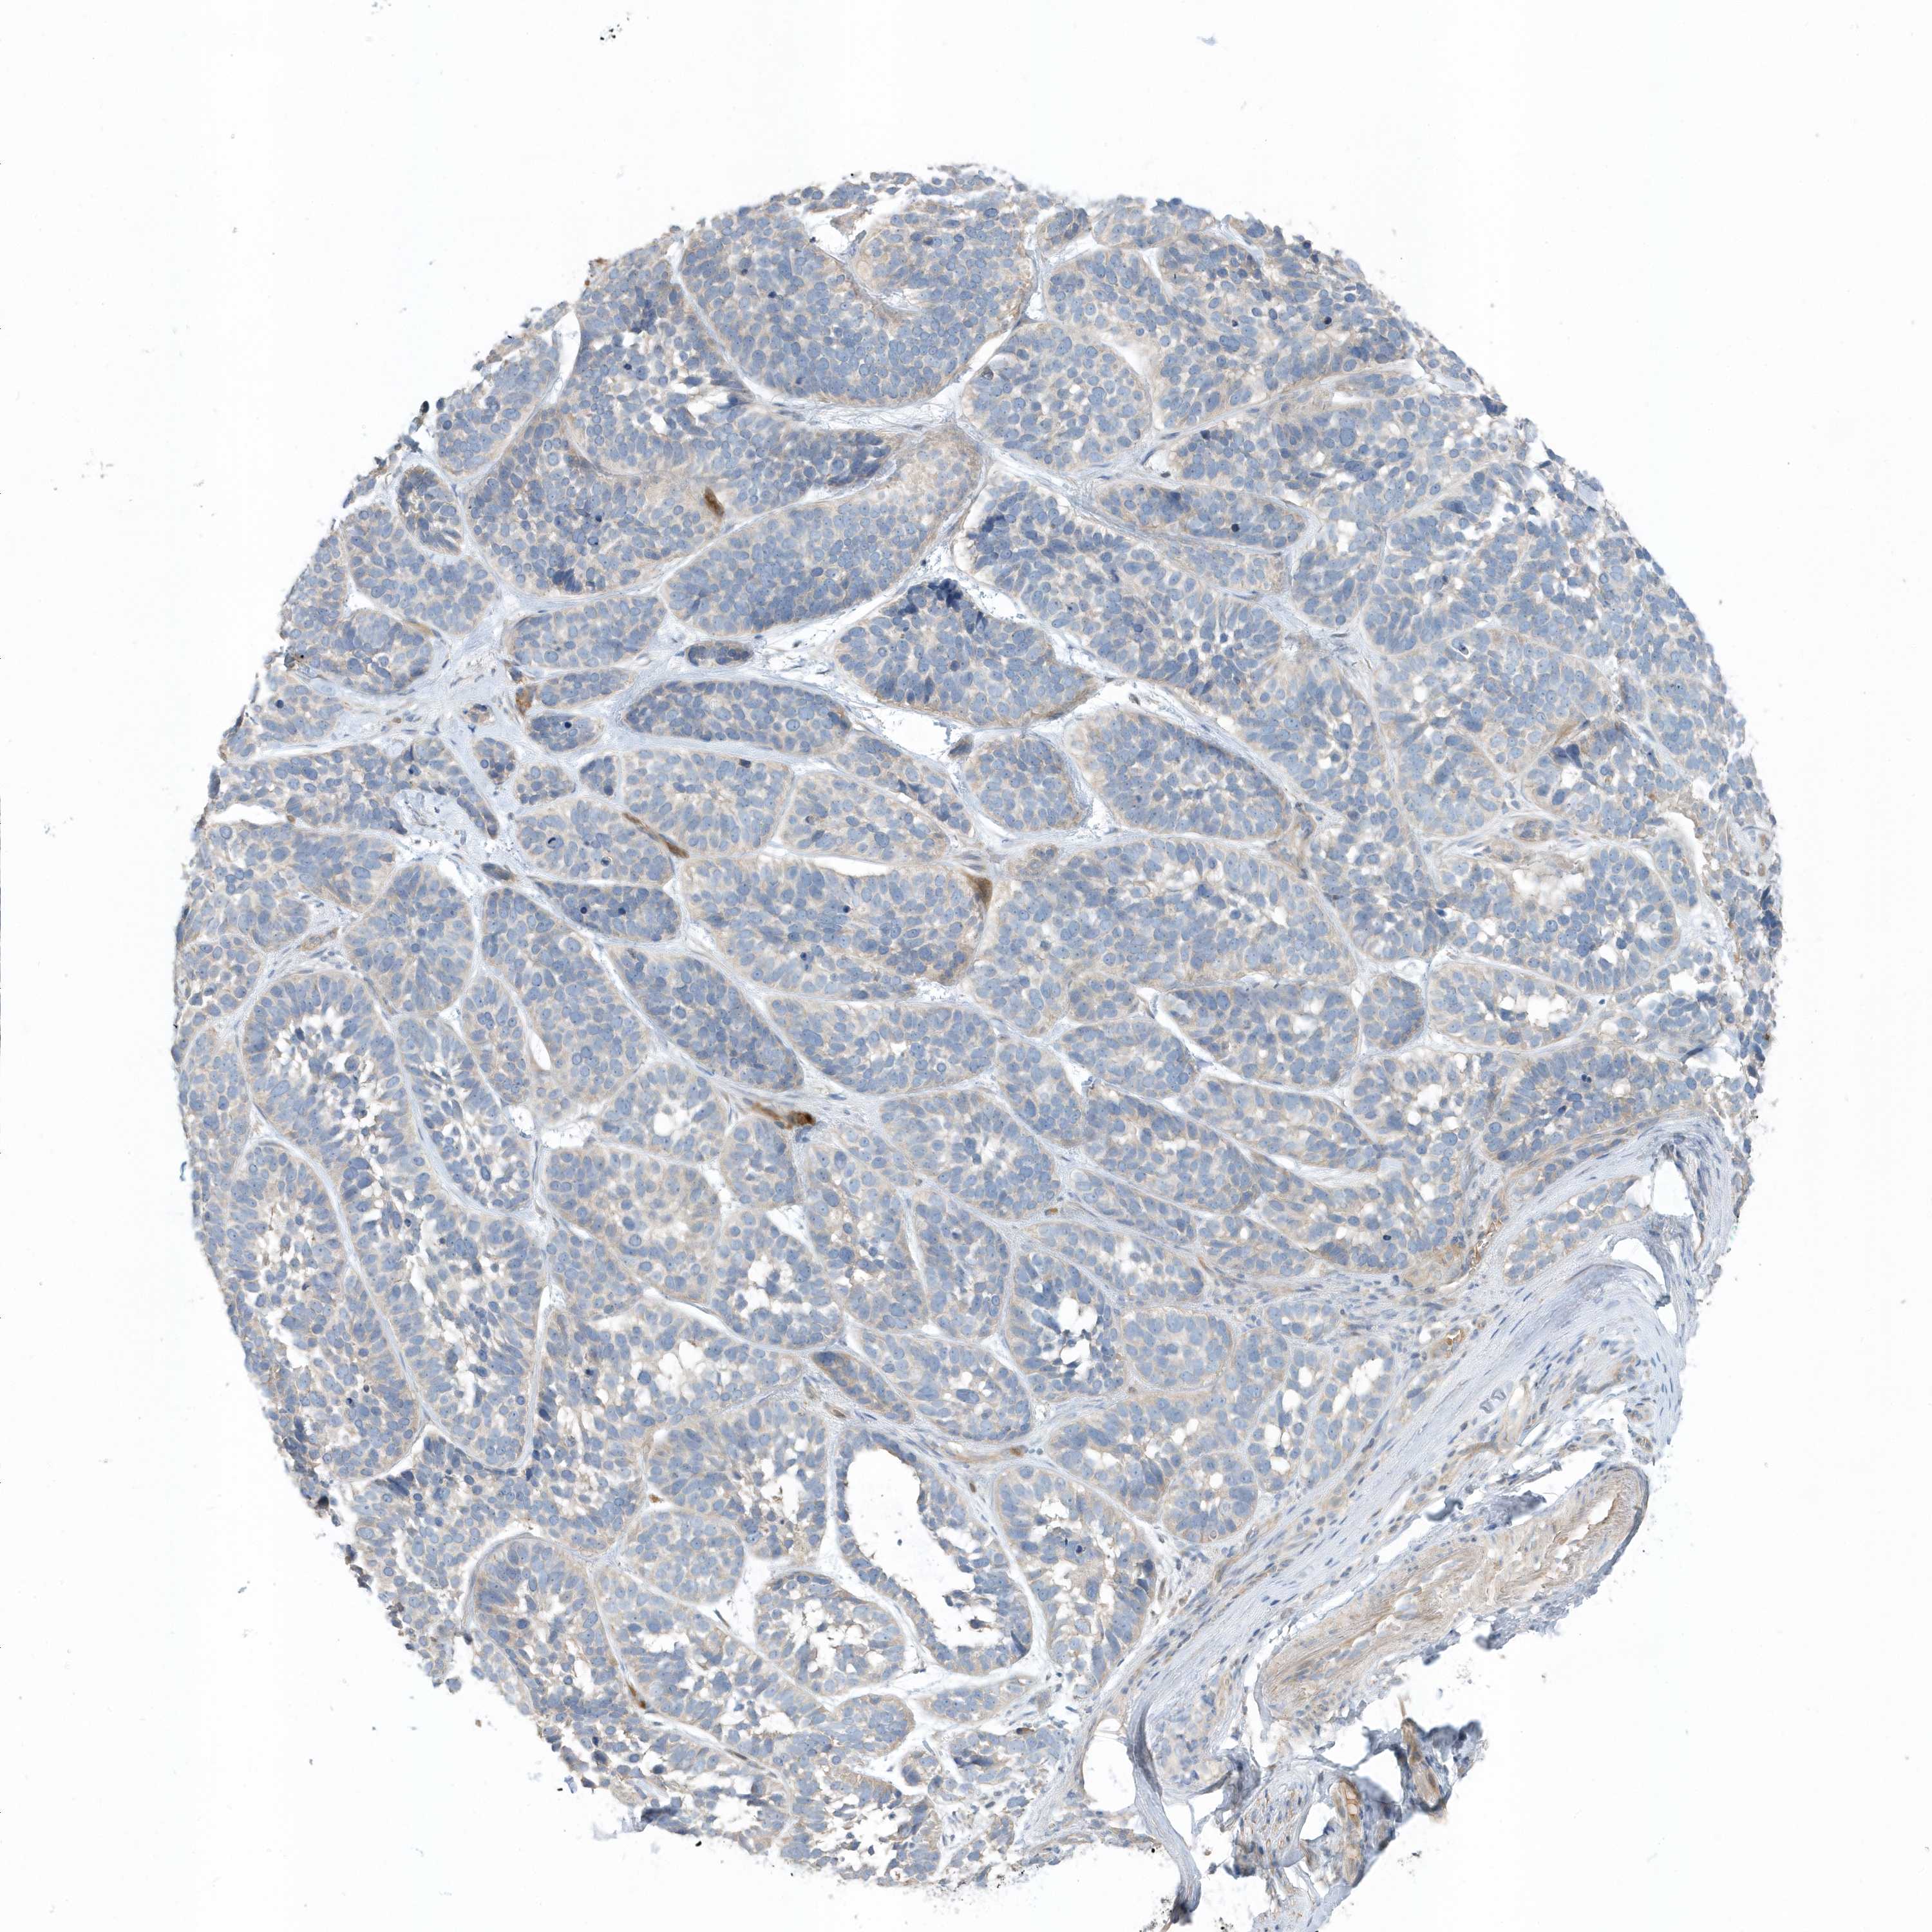

Basal cell and squamous cell cancer

SKIN CANCER - Protein expressioni

A mouse-over function shows sample information and annotation data. Click on an image to view it in a full screen mode. Samples can be filtered based on level of antibody staining by selecting one or several of the following categories: high, medium, low and not detected. The assay and annotation is described here.

Antibody stainingi

Antibody staining in the annotated cell types in the current human tissue is reported as not detected, low, medium, or high, based on conventional immunohistochemistry profiling in selected tissues. This score is based on the combination of the staining intensity and fraction of stained cells.

Each image is clickable and will lead to virtual microscopy that enables deeper exploration of all samples and also displays staining intensity scores, fraction scores and subcellular localization as well as patient and tissue information for each sample.

Antibody HPA035844

Antibody HPA035845

Staining

Not detected

Negative

None

Basal cell carcinoma